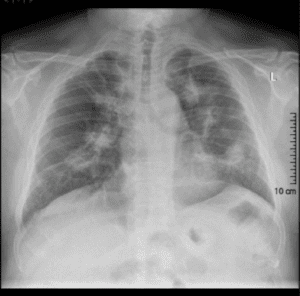

A 42-year-old woman has two episodes of haemoptysis. She also reports two months of sinusitis with pain, stuffiness and nose bleeds. She has some loosening of her teeth and painful oral ulceration. Previously, she noticed a rash and nodules over her elbows, but they have disappeared. Investigations: Chest X-ray: see image Urinalysis: occasional red cell casts

Granulomatosis with polyangiitis (GPA) is the most likely diagnosis based on the history of sinusitis, oral ulceration, and haemoptysis and the bilateral pulmonary nodules on chest X-ray. GPA is a rare autoimmune disease that affects small blood vessels in the body, causing inflammation and tissue damage. The presence of red cell casts in the urinalysis suggests renal involvement, which is also common in GPA. The other conditions listed are less likely to explain the patient's symptoms and findings.